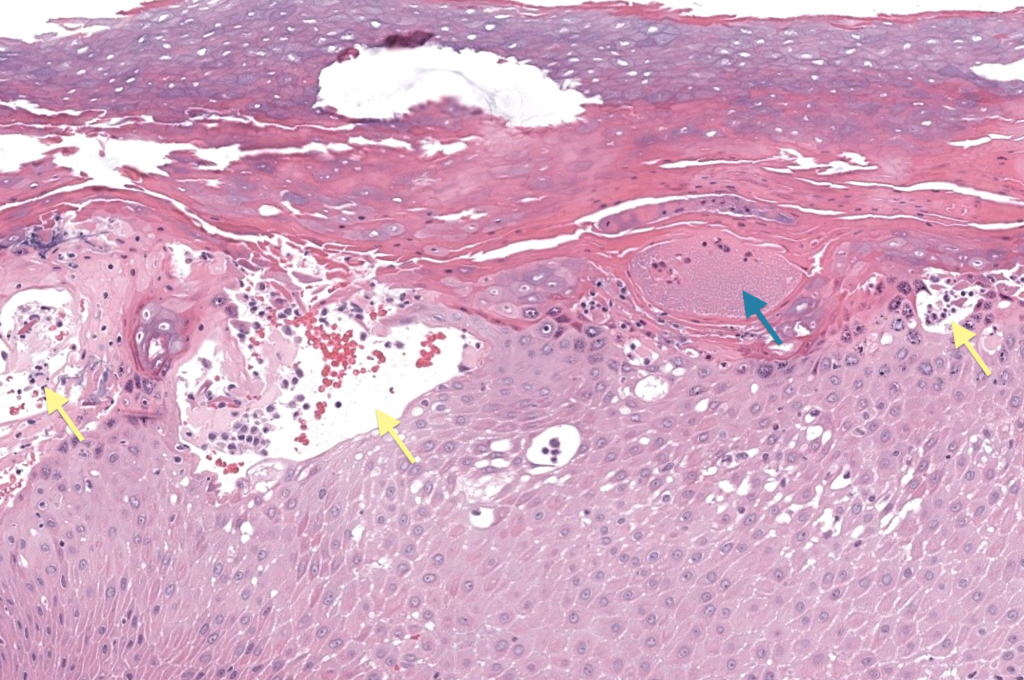

- Si atípico: biopsia H&E ± DIF para diferenciales ampollosos/psoriasis. Wollina 2010